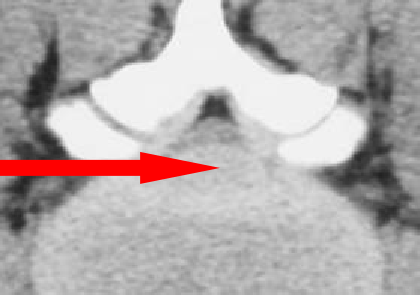

椎间盘造影

常见的五种典型的椎间盘变化